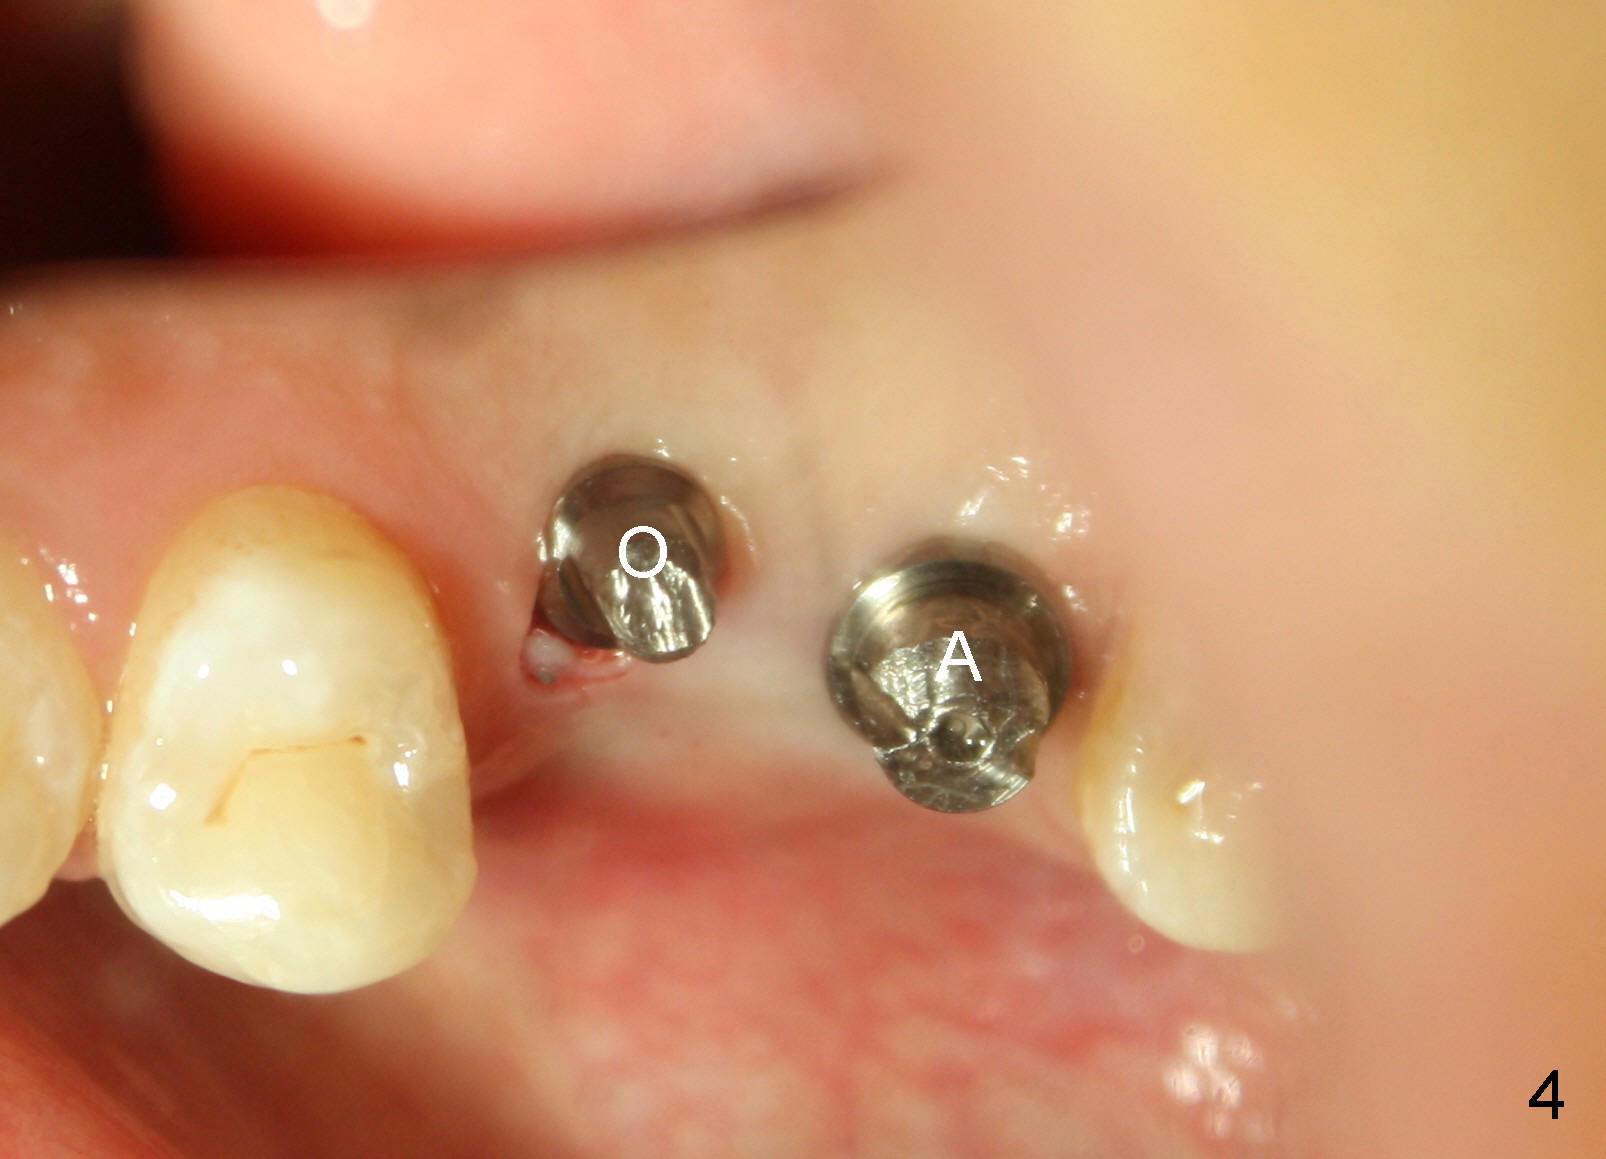

The patient returns for #13,14 implant placement. The ridge appears to be wide buccolingually (Fig.1 mirror view). A 4 mm tissue punch is used for access at the sites of #13 and 14. Osteotomy is initiated by using 3 mm trephine bur at the depth of 4 mm at both sites; 2 mm pilot drill is used to continue osteotomy at 8 mm deep at the site of #13. Sinus lift is accomplished by using tapered osteotomes 2,3 mm 6 mm deep, followed by 4.5x11 mm tap (Fig.2 T); 2 mm pilot drill (P) is reinserted into #13 osteotomy site with inadvertently penetrating the sinus floor. When the tap is removed from the site of #14, the sinus membrane is also found to be perforated. The sinus membrane at both sites is repaired by insertion of collagen dressing before bone graft. A 4x11 mm one-piece implant is placed at the site of #13 slowly hoping that it does not re-perforate the sinus membrane (Fig.3 O). Due to limited restorative height, the abutment portion of the one-piece is expected to be trimmed (Fig.4 O). In case of implant complication or failure, the implant may be difficult to be removed. Therefore the implant at the site of #14 is two piece one (Fig.4,5 I/A, 5x11 and 4x3 mm, respectively). The insertion torques for #13 and 14 are 35/40 and >60 Ncm. Immediate provisionals are canceled mainly because of patient's inability to open wide for long. Perio dressing is placed instead after adjustment of the height of the abutments. The patient experiences one episode of light nasal hemorrhage a few hours postop. Although the patient takes Amoxicillin for 1 week periop, the implant at the site of #13 dislodges 1 months postop (Fig.5). Immediate re-placement with a larger 2 piece one is canceled because of mild infection mesiobuccal to the implant at the site of #14 (Fig.6 >). Exploration around the latter implant reveals possible thread exposure in a small area. After copious irrigation with normal saline, Arestin is placed. Two months post exfoliation, the site is re-entered (Fig.7,8). There is a lingual defect. Osteotomy is initiated as buccal as possible. A 4.5x11 mm tapered tap penetrates the sinus floor without tearing the membrane (Fig.9). The same-sized implant is placed (25/30 Ncm) with sinus lift (Fig.10 *). The lingual defect is bone grafted. There is dehiscence lingually 7 days postop (Fig.11). Impression for final restoration is taken 1.5 months postop because of pending wedding. The crown has been in function for 2.5 months.